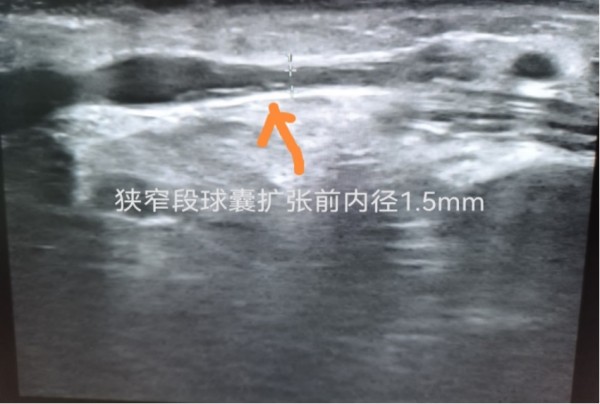

患者周某,老年女性,既往有肾功能异常病史3+年,已维持性血液透析治疗8月,合并糖尿病、糖尿病视网膜病变、冠心病、高血压等多种基础疾病。该患者近2月来透析流量差,穿刺困难,经过彩超检查发现左腕部动静脉内瘘流出段瘘静脉狭窄,桡动脉管径细,有指征行球囊扩张术,如果不进行手术,可能导致透析不充分,透析质量越来越差,最终并发各种严重并发症,故解决患者血管通路问题迫在眉睫。经过与患者及家属详细沟通,同意行球囊扩张术。现已成功为该患者实施了左腕部动静脉内瘘狭窄段球囊扩张术,为患者重新开通了生命线。术后触诊检查震颤明显,听诊杂音响亮,手术取得圆满成功。